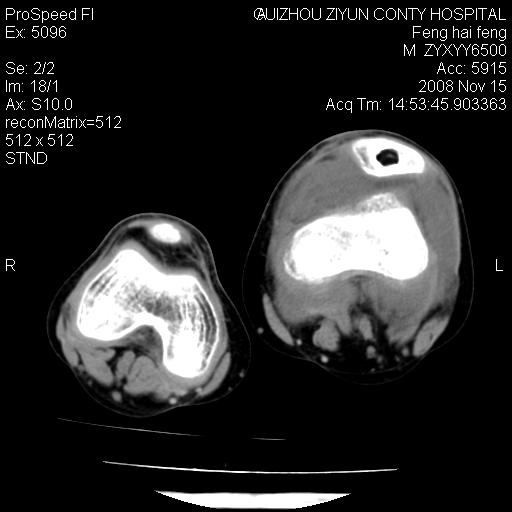

标题: CT16656:M 14Y 左膝关节肿胀一年余。其余病史不详。 [打印本页]

标题: CT16656:M 14Y 左膝关节肿胀一年余。其余病史不详。

考虑左侧髌骨结核;左膝关节滑膜肿胀、增厚,关节囊积液。

左膝滑膜型关节结核可能性大!支持!滑膜型关节结核主要ct表现:关节囊肿胀,积液,关节面见小破坏灶,并见点状死骨!

好大的左腿!考虑左侧髌骨结核,左膝关节滑膜肿胀、增厚,关节囊积液。

左侧髌骨结核;左膝关节滑膜肿胀、增厚,关节囊积液